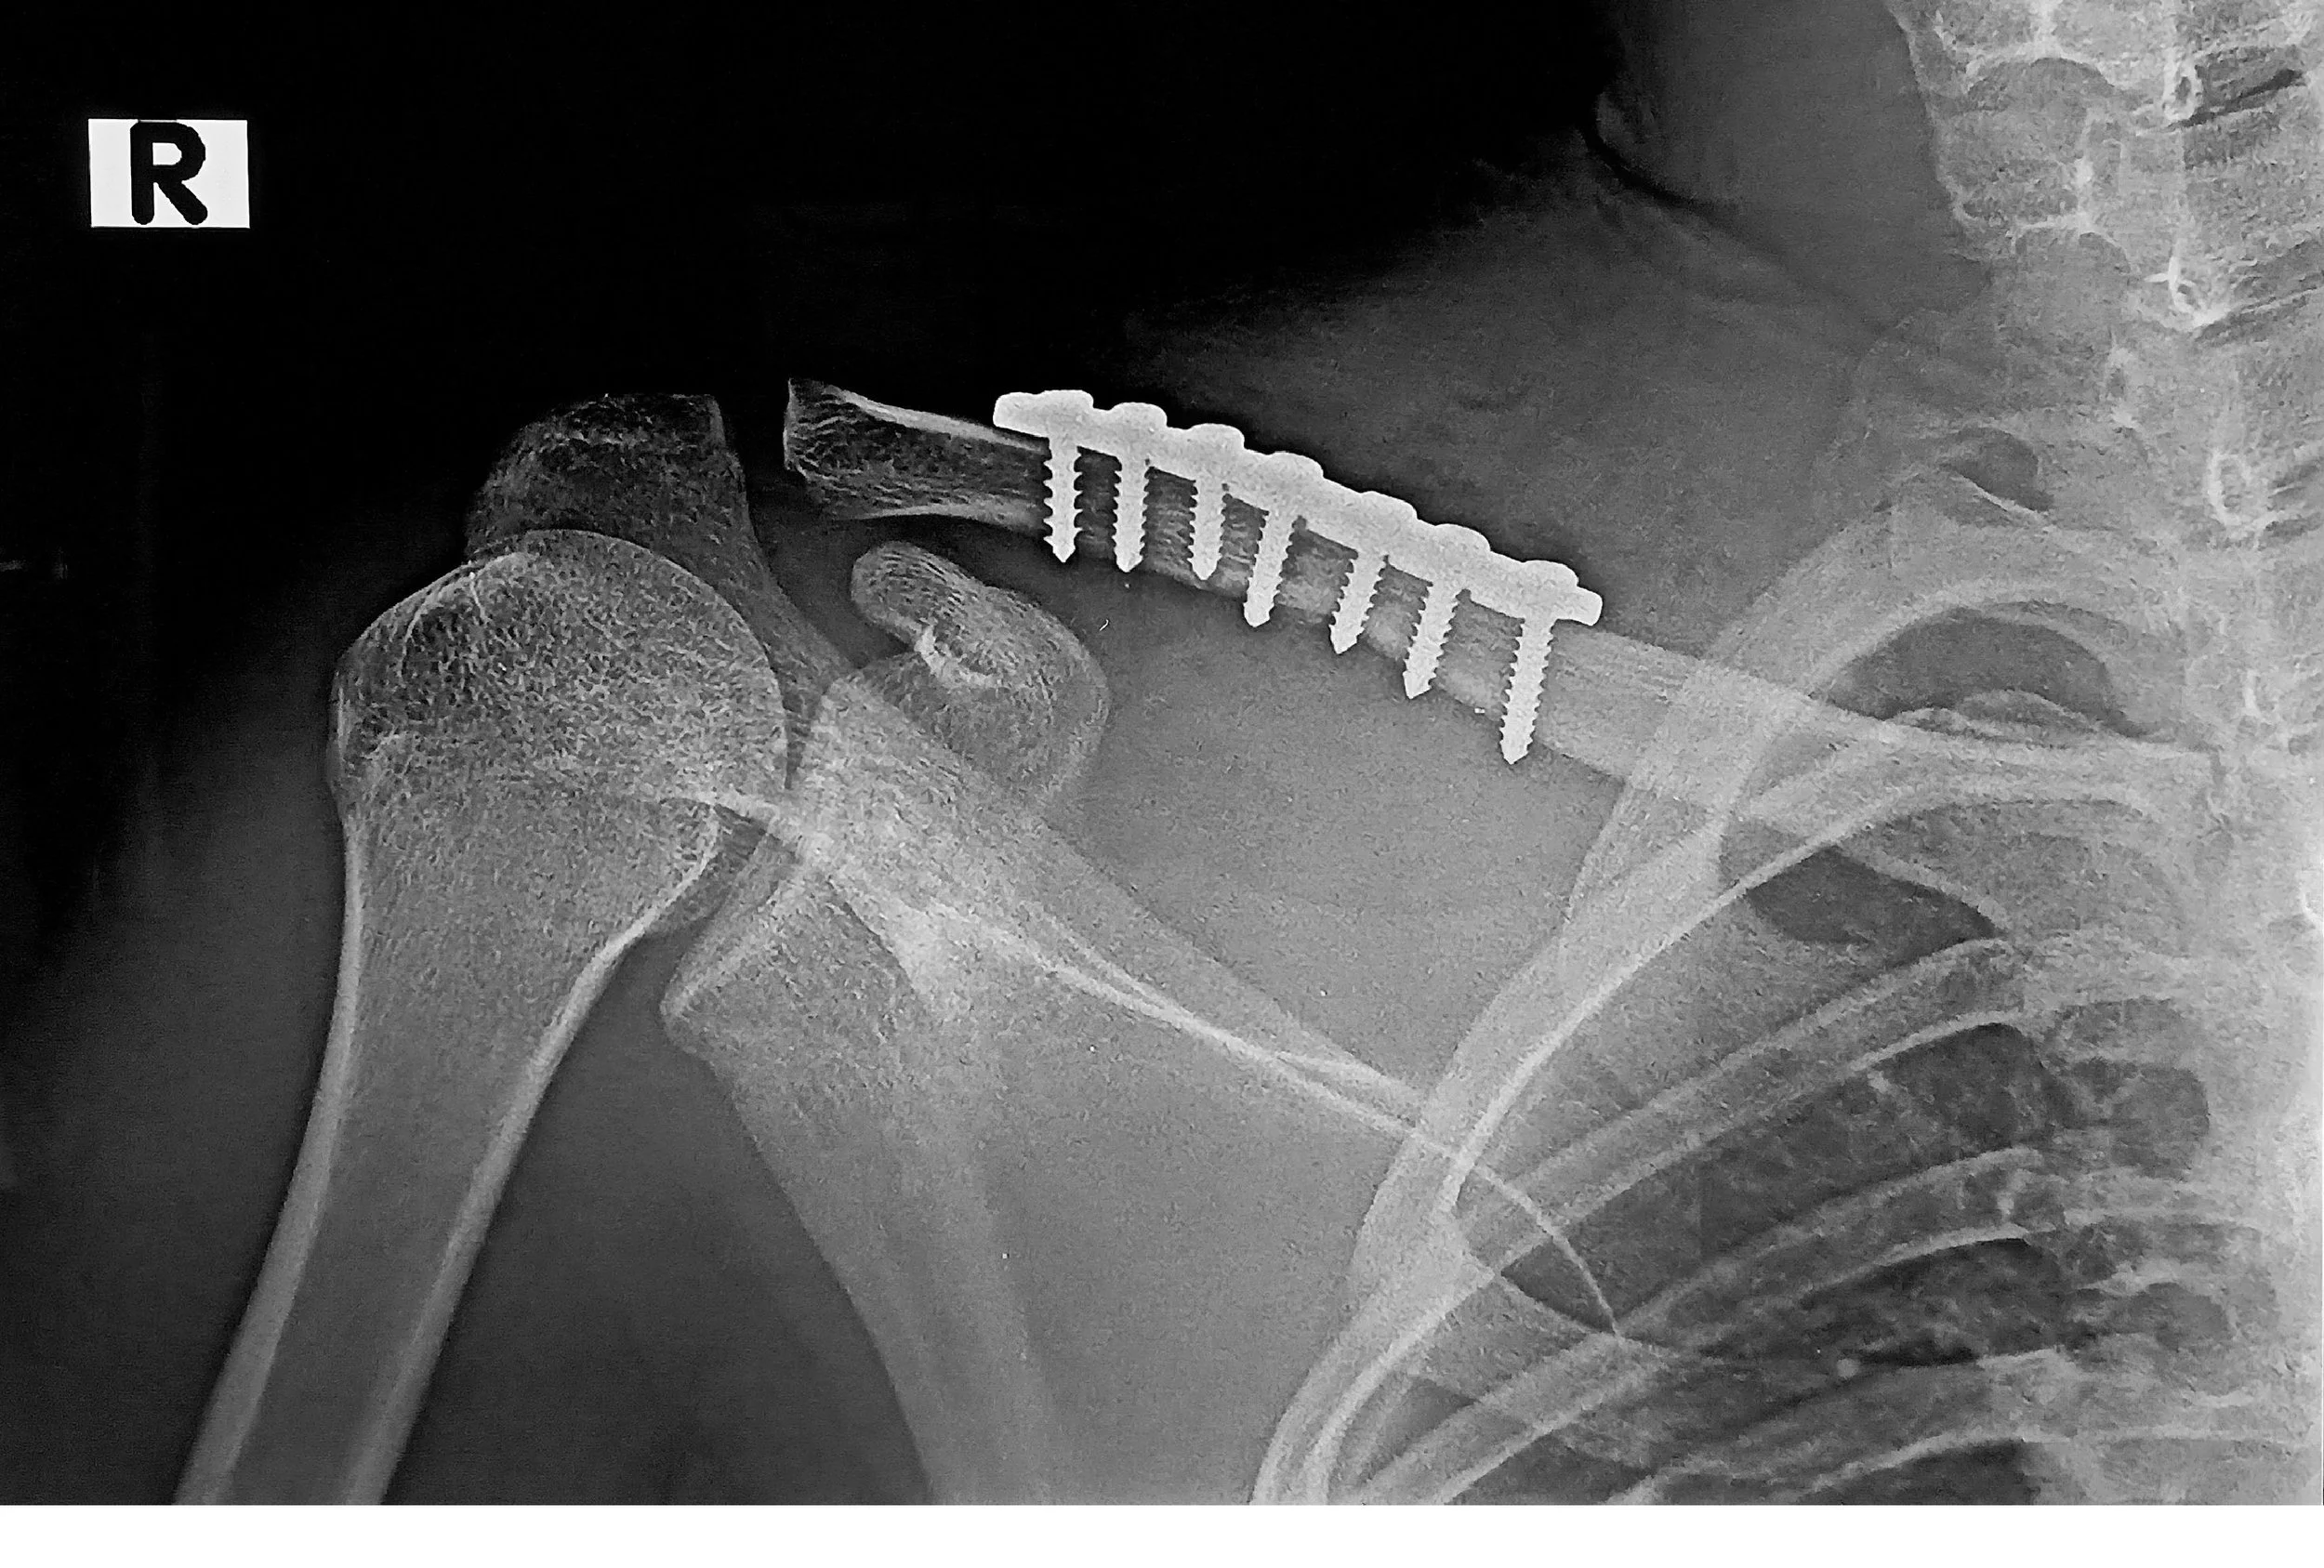

X-ray image of a shoulder with a metal screw and plate fixation for a broken clavicle. - Dr. Kevin Wall, Richmond, VA

• Fixation: A low-profile, contoured titanium or stainless steel plate is secured across the fracture using multiple screws. This acts as an internal scaffold, providing rigid stability that allows the bone to knit back together. For complex fractures or poor bone quality, specialized "locking plates" are used to ensure the screws do not loosen during the healing process.